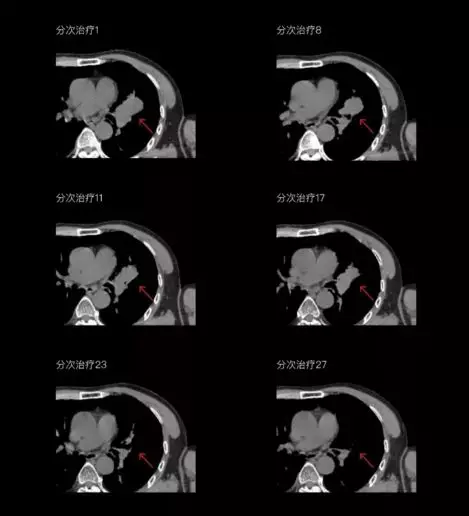

一體化CT-linac讓自適應(yīng)放療ART概念變?yōu)楝F(xiàn)實?;颊呷煶虪顟B(tài)監(jiān)控,適時在線調(diào)整治療計劃,精準(zhǔn)控制治療劑量,為患者動態(tài)定制個體化治療方案。uAI賦能智能勾畫和自動計劃,秒級勾勒靶區(qū)和危及器官,大幅縮短自適應(yīng)放療時間。

聯(lián)影CT-linac全程監(jiān)測治療過程病灶的變化,及時調(diào)整和優(yōu)化治療方案